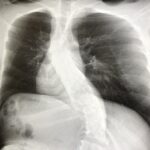

【実際の写真7枚】背骨のレントゲン